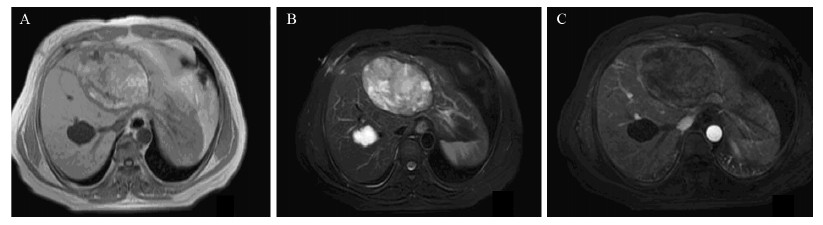

患者于2013年3月21日行CT引导下肝囊肿穿刺引流术,见囊液为暗褐色、无异味黏稠液体。术中及术后囊液多次免疫学检测显示:CA19-9均呈超高水平表达( > 10 000 u/ml)、其中术中留取标本中CA19-9值达15 947 u/ml。引流后间断3次留取囊液行细胞学检查,结果均提示可见变性坏死物,未检测到细菌、肿瘤细胞和寄生虫;CA19-9水平也呈逐渐下降趋势,术后第3天、6天分别为10 813 u/ml、8 784 u/ml。引流一周后复查上腹MRI提示:肝左叶可见10.6 cm×6.8 cm大小异常信号肿物影,T1WI呈不均匀稍高信号、T2WI呈不均匀高信号,边界尚清,增强后未见明显强化、周围胆管轻度扩张,见图 2。血管、胆管受压以及囊液CA19-9超高水平表达不能排除是否为恶性肿瘤性囊性病变可能,鉴别诊断较为困难,拟转至外科行手术治疗。

| A:the cyst appeared as inhomogeneous slight hyperintense signal on T1 weighted images,with a clear demarcation;B:the cyst appeared as inhomogeneous hyperintense signal on T2 weighted images,the intrahepatic bile duct of left lateral lobe was dilated;C:the cyst's wall did not appear significantly enhanced,even on the dynamic contrast enhanced MRI scan images 图 2 肝囊肿手术切除前MRI Figure 2 MRI images of hepatic cysts before surgical resection |